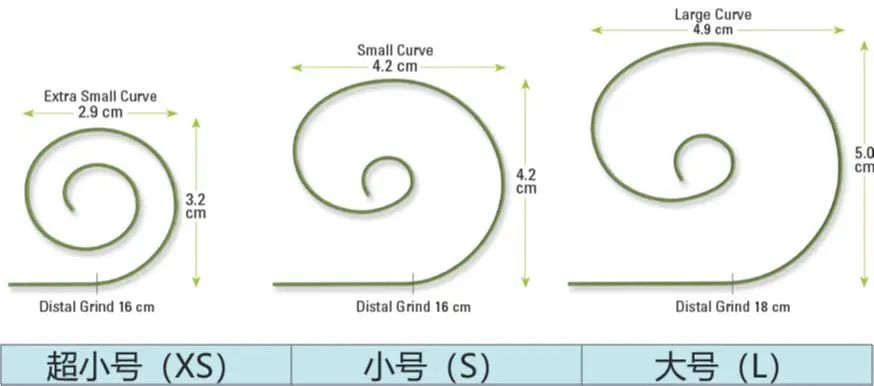

手术策略

XS超小号 SAFARI² 导丝

猪尾指引下SAFARI²导丝在左室准确定位

SAFARI²头端双圈结构完全显现,并有一定压缩;头端随心室Pacing。

SAFARI²为全球第一款预塑性导丝,全球应用超50w例。预塑形一方面节约塑性时间,另一方面降低因塑性不当引起的心室穿孔等并发症。

SAFARI²顺应性好,在本例手术中,很好的帮助球囊扩张、瓣膜定位、瓣膜释放。

SAFARI²具有极好的安全性和支撑性,在本例手术中,可精准定位瓣膜在预设的位置。